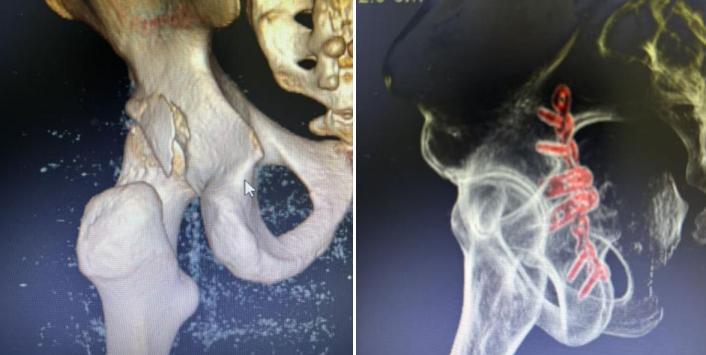

图片

(▲手术前 手术后)